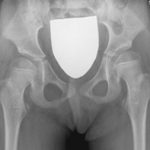

The surgical technique consists of inserting a cannulated screw into the femoral neck to prevent the femoral head from progressively move out of its natural socket.

In all the patients, surgery allowed to perfectly reach the goal of a total containment of the hip inside the acetabular socket persistent over the years.

The advantages of this unique and never described before intervention are the possibility of performing it in outpatient procedure with an average hospitalization time of 2.30 hours. The patient feels no pain thanks to the minimally invasive–percutaneous surgery and the possibility of immediate loading.